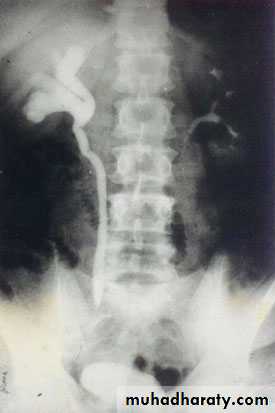

Laterally displaced ureters

Medially displaced ureters